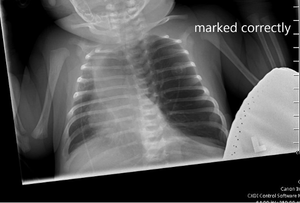

On physical examination, the patient appeared to be in significant respiratory distress. Her oxygen saturation was 96% on high-flow nasal cannula.